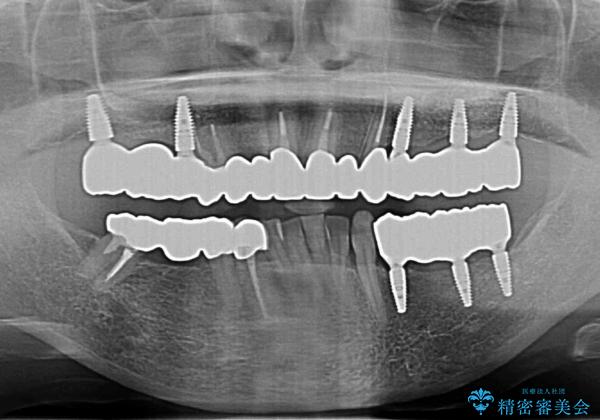

多発した虫歯による咬合崩壊 インプラントを用いた全顎治療

歯の破折・再発した大きな虫歯・根尖病変・歯の欠損、これらの問題を根管治療・歯周外科・インプラント治療・セラミック補綴を行うことで一つづつ解決し安定した咬合状となるよう治療を進めます。

- 440万円(税込)費用は治療当時の料金となります

口腔内全体を治療する全顎治療は、期間も長く外科を行う回数も多いためしっかりと通っていただくことが必要不可欠になります。

治療に加えて歯ブラシも上手になることが、治療した歯を長持ちさせるのに必要な要件となります。